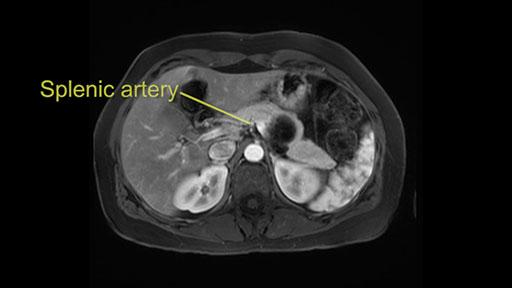

Other slowing down moments with this procedure include dissection of the splenic vein and splenic artery. These are technically challenging moments and important moments where care needs to be taken. Not only to avoid bleeding and injury to the vessels but also to ensure an adequate margin.

The lesion itself is quite adjacent to and abuts the splenic vein and therefore we need to anticipate that these two structures will be intimately related and possibly impossible to separate between the two.

The second slowing down moment or consideration I give to a distal pancreatectomy is the anatomy of the portal vein and the splenic artery. And so I look here and the anatomy is pretty straightforward. The splenic vein comes off normally and runs behind the pancreas and I can see the artery superior to that, again coming off in a normal manner from the celiac axis. So those two things, the portal vein and the splenic artery will be taken normally in this procedure.